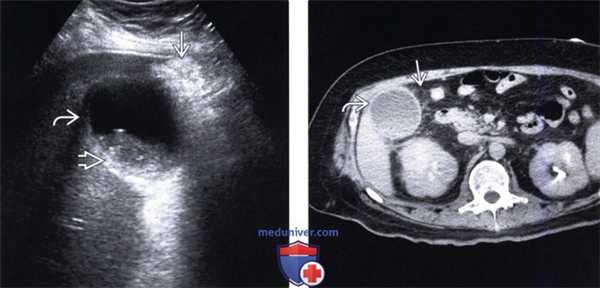

(Справа) При гепатобилиарной сцинтиграфии у женщины 48 лет с жалобами на боль в правом подреберье, с подтвержденным при оперативном вмешательстве острым холециститом, определяется накопление радиофармпрепарата (РФП) в кишечнике, отсутствие накопления РФП в желчном пузыре, а также едва заметный симптом «ободка» в области ямки желчного пузыря. Персистирующее накопление РФП около желчного пузыря может быть обусловлено отеком тканей и стазом желчи. (Слева) На аксиальной КТ с контрастным усилением определяется утолщение стенки желчного пузыря с наличием небольшого конкремента в его полости, визуализируется свободная жидкость возле его стенок в сочетании с повышением плотности перипузырной жировой ткани — совокупность признаков, позволяющих предположить острой холецистит.

(Справа) На аксиальной КТ с контрастным усилением у женщины 37 лет определяется утолщение стенок желчного пузыря и повышенное накопление контраста в области его ямки. Гиперемия паренхимы печени вокруг желчного пузыря аналогична симптому «ободка» при гепатобилиарной сцинтиграфии.

(Левый) При остром холецистите на поперечном УЗ срезе визуализируются смещающиеся книзу под действием гравитации конкременты желчного пузыря и сладж. Обратите внимание на утолщение стенки желчного пузыря и воспаленную эхогенную жировую клетчатку с медиальной стороны.

(Правый) Этот же пациент. Аксиальная КТ с контрастным усилением. Определяются растянутый желчный пузырь с утолщенной стенкой В, смещающиеся книзу под действием гравитации конкременты и сладж. Обратите внимание на исчерченность перипузырной жировой клетчатки.